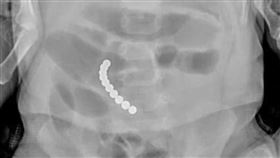

男童誤吞61顆磁球 腸道中串成項鍊

大陸黑龍江哈爾濱日前發生兒童誤食事件!一名6歲男童誤...